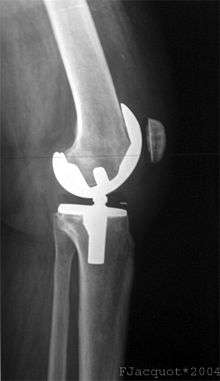

X-ray of total knee replacement, anterior-posterior (front to back) view.